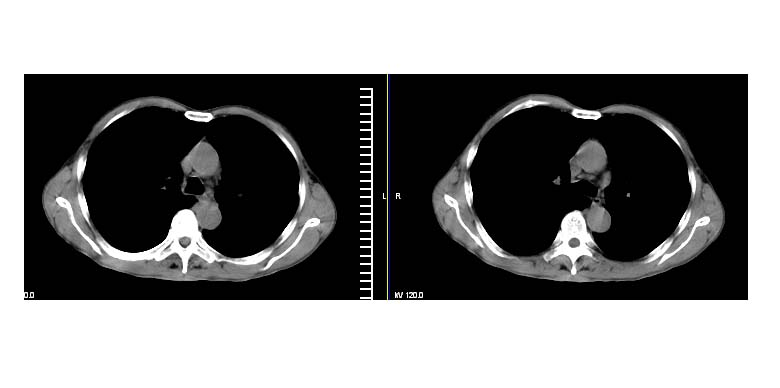

标题: CT11019:男性,66岁。发烧5-6天。治疗后无明显好转。 [打印本页]

标题: CT11019:男性,66岁。发烧5-6天。治疗后无明显好转。

阻塞性肺炎并不张,建议抗炎治疗后复查或增强

支持抗炎后复查,无明显肿大淋巴结,胸膜也无改变

考虑左肺下叶炎症合并叶间裂积液,建议抗炎治疗后复查

左侧胸廓偏小,左下梭形高密度影,考虑阻塞性肺炎.

明明是斜裂胸膜积液,为何都考虑阻塞性肺炎、肺不张(边缘内凹,而本例是外凸)。